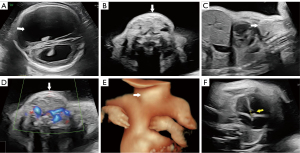

Ultrasonography at our institution revealed the following: Bilateral lateral ventriculomegaly, with a left ventricular width of 47 mm and a right ventricular width of 23 mm (Figure 1A), and a “dumbbell-shaped” moderately echogenic mass (26 mm × 15 mm) anterior to the fetal trachea, encircling the airway with homogeneous internal echogenicity. Color Doppler flow imaging showed no significant vascularity in the central portion of the mass but sparse flow signals peripherally (Figure 1B-1D, and Videos 1,2). Three-dimensional surface rendering confirmed anterior cervical swelling (Figure 1E), a narrowed fetal thoracic cage (transverse thoracic diameter: 48 mm) with an increased cardiothoracic ratio (cardiac transverse diameter: 32 mm), and a ventricular septal defect (2.5 mm) (Figure 1F). Persistently extended upper limbs and a fixed cross-legged lower limb posture without dynamic changes were also observed (Figure 2A,2B and Video 3). The metatarsal bones were poorly visualized, with only phalanges identified in both feet (Figure 2C,2D, and Video 4). The amniotic fluid assessment showed a maximum vertical pocket depth of 106 mm and an amniotic fluid index of 368 mm. The ultrasonographic diagnosis was as follows: (I) severe fetal hydrocephalus; (II) an anterior cervical hyperechoic mass, suggestive of thyroid goiter; (III) a narrowed thoracic cage with increased cardiothoracic ratio and ventricular septal defect; (IV) metatarsal hypoplasia and fixed limb postures; and (V) moderate polyhydramnios. Prenatal umbilical vein puncture confirmed fetal hypothyroidism (TSH: 11.32 mU/L; normal range, 0.38–4.34). The family opted to terminate the pregnancy at an external institution, as in addition to the fetal malformation, the patient was unmarried, and the pregnancy unplanned. Documentation provided by the family indicated that the autopsy findings were consistent with our ultrasound diagnoses, though post-procedure images were unavailable.